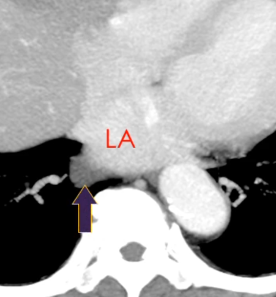

Sinus Oblique

Sinus Veineux Pulmonaire